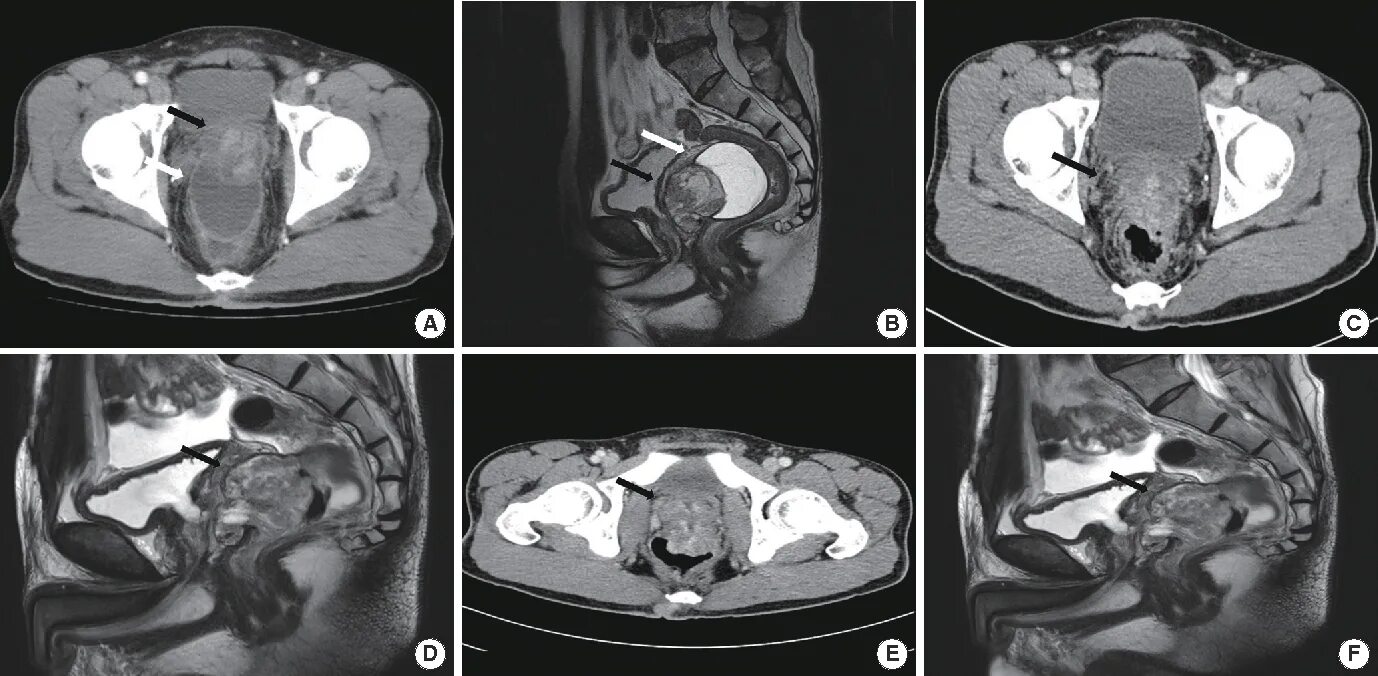

Мрт симптомы